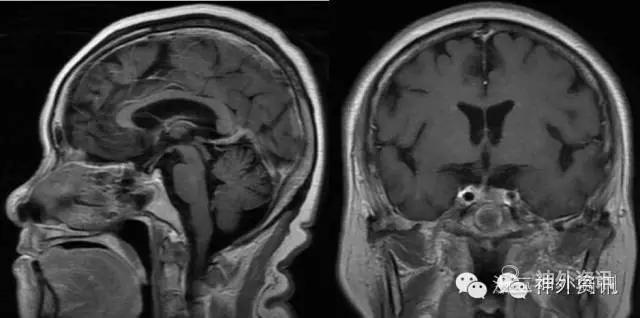

2月前患者睡眠时突发头痛,为前额部胀痛,程度剧烈,影响睡眠,伴恶心呕吐,呕吐物为胃内容物,无寒战发热,无意识障碍,无肢体抽搐。于当地医院就诊,查头颅CT提示垂体占位病变,因担心手术风险未治疗。此后头痛反复发作,2周前突发左眼失明,无眼痛,无恶心呕吐,来我院复查头颅CT及MRI,提示“垂体大腺瘤”(图1),要求手术收住入院。

图1. 头颅CT提示鞍区等密度病变,MRI显示T2像等低混杂信号,T1像强化明显,内有囊变,左侧部分侵袭海绵窦。